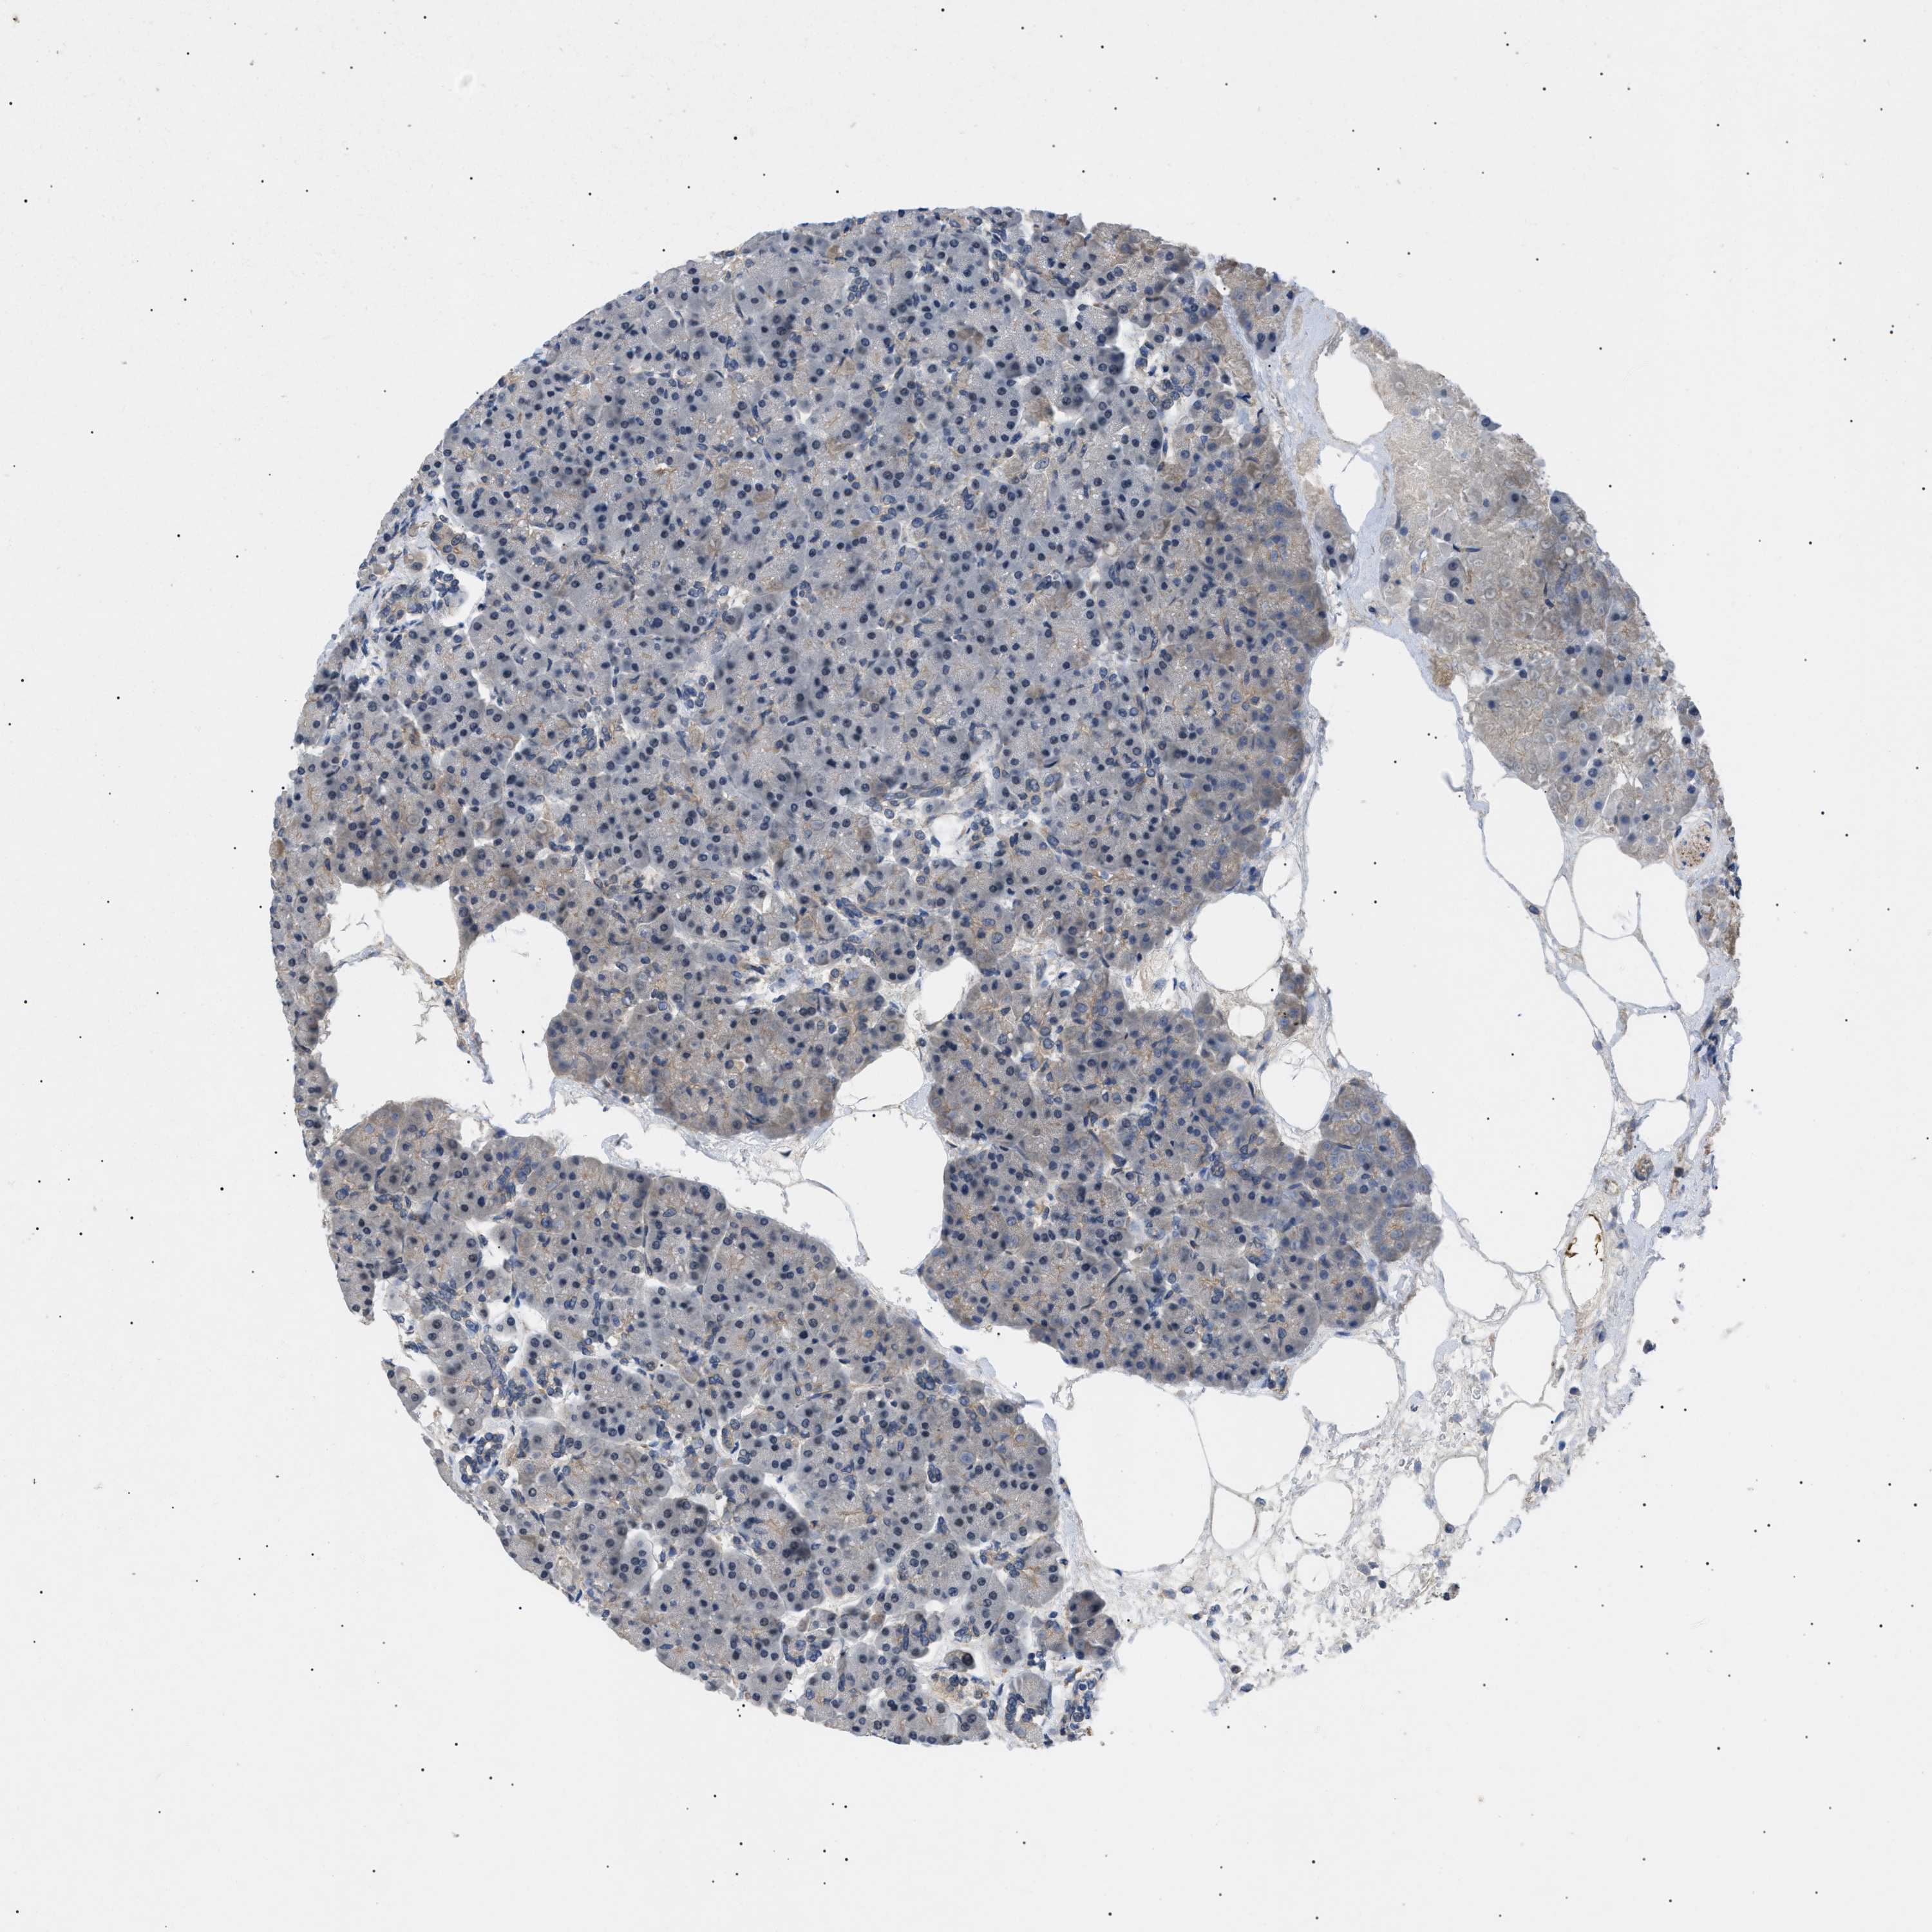

PANCREAS - Antibody stainingi

Antibody staining in the annotated cell types in the current human tissue is reported as not detected, low, medium, or high, based on conventional immunohistochemistry profiling in selected tissues. This score is based on the combination of the staining intensity and fraction of stained cells.

Each image is clickable and will lead to virtual microscopy that enables deeper exploration of all samples and also displays staining intensity scores, fraction scores and subcellular localization as well as patient and tissue information for each sample.

Antibody HPA007216

Exocrine glandular cells Medium

Pancreatic endocrine cells Medium